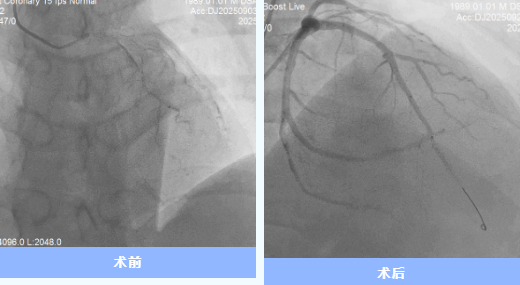

患者到院后,團(tuán)隊(duì)立即實(shí)施急診PCI手術(shù)。術(shù)中造影顯示前降支近端完全閉塞,雖經(jīng)球囊擴(kuò)張、血栓抽吸等操作,仍出現(xiàn)“無(wú)復(fù)流”現(xiàn)象。IVUS檢查提示冠脈內(nèi)彌漫性血栓,團(tuán)隊(duì)討論后決定暫不植入支架,先開(kāi)展強(qiáng)化抗栓抗板治療,待后續(xù)復(fù)查造影。

9月24日,經(jīng)過(guò)充分的術(shù)前評(píng)估,心內(nèi)科一病區(qū)介入團(tuán)隊(duì)為代先生復(fù)查冠脈造影并于前降支成功植入支架1枚。